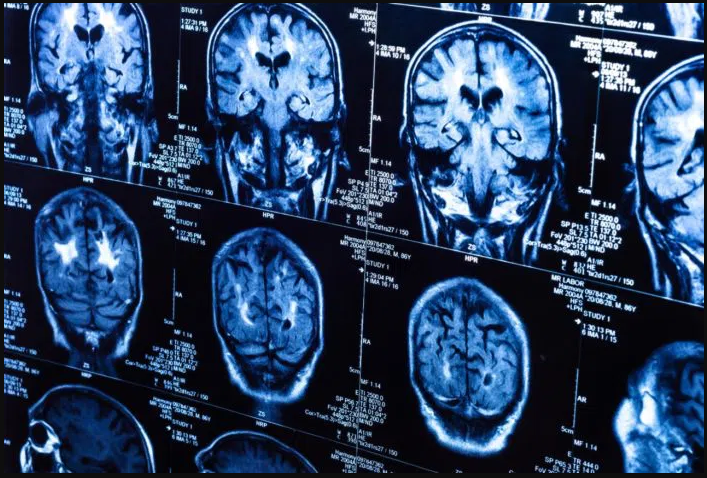

A traumatic brain injury is caused by a jolt to the head that disrupts normal brain functioning. These types of head injuries may be mild, moderate, or severe.

Severe head injuries may cause a person to be unconscious for an extended time and/or cause memory loss. A severe TBI may involve torn brain tissue, bleeding, and other damage to the brain that can lead to long-term complications or death.

Head injuries can have a serious impact on a person’s quality of life. A traumatic brain injury, or TBI, can impair memory, sensation, emotional functioning, or coordination. Severe TBI may also result in death. Approximately 176 Americans die each day from TBI-related causes, according to the CDC.